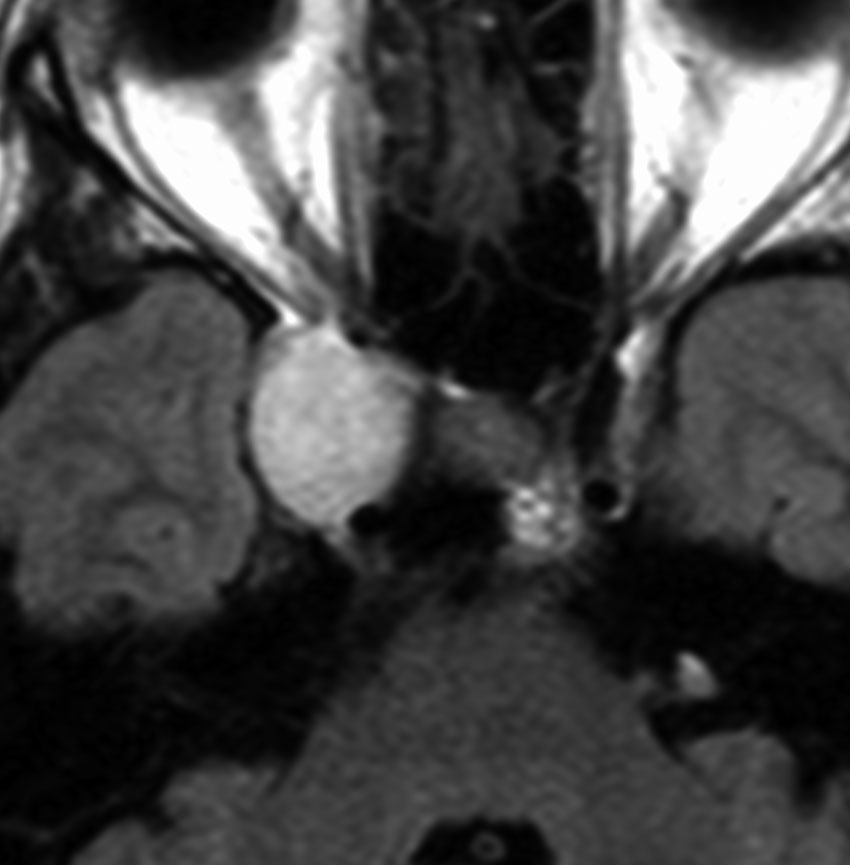

脳幹部の海綿状血管腫を手術するとき

左上のT2*でみられるように多発性海綿状血管腫の成人男性に発生した中脳海綿状血管腫です。複視と歩行失調で発症して,数回の脳幹部出血を繰り返し,水頭症になったために第3脳室開窓術がなされました。それでも出血は止まらず、両側の動眼神経麻痺による両側眼瞼下垂,歩行失調,嚥下障害などさまざまな中脳症状が進行しました。

しかたがないので手術で摘出しました。なんとか眼瞼が持ち上がるようになり歩行も可能で嚥下もできます。幸いだったのは感覚路(脊髄視床路)の障害による体性疼痛が生じなかったことです。

手術は経テント法 OTA という手法でした(クリックと手技が書いてあります)

片方の下丘の損傷だけでは神経脱落症状が出ないので,中脳内部の腫瘍を摘出するには下丘という狭い場所を切開して入りますが,この患者さんは左上丘も出血のために破壊されていて,間口が広かったといえます。でもこの手術は難しすぎるので決して積極的にはしません。